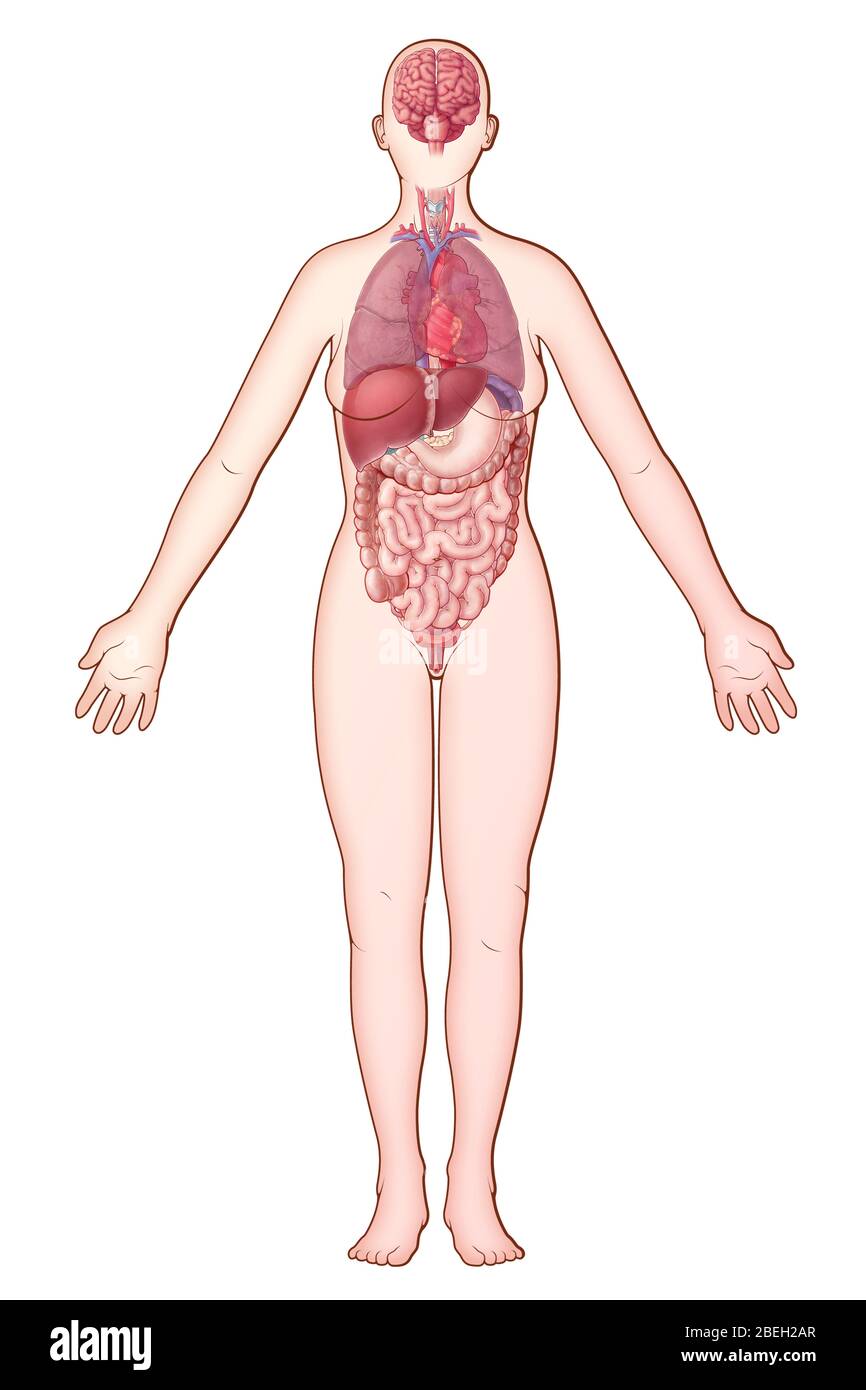

Organ Systems, illustration Stock Photohttps://www.alamy.com/image-license-details/?v=1https://www.alamy.com/organ-systems-illustration-image353187599.html

Organ Systems, illustration Stock Photohttps://www.alamy.com/image-license-details/?v=1https://www.alamy.com/organ-systems-illustration-image353187599.htmlRM2BEH2AR–Organ Systems, illustration